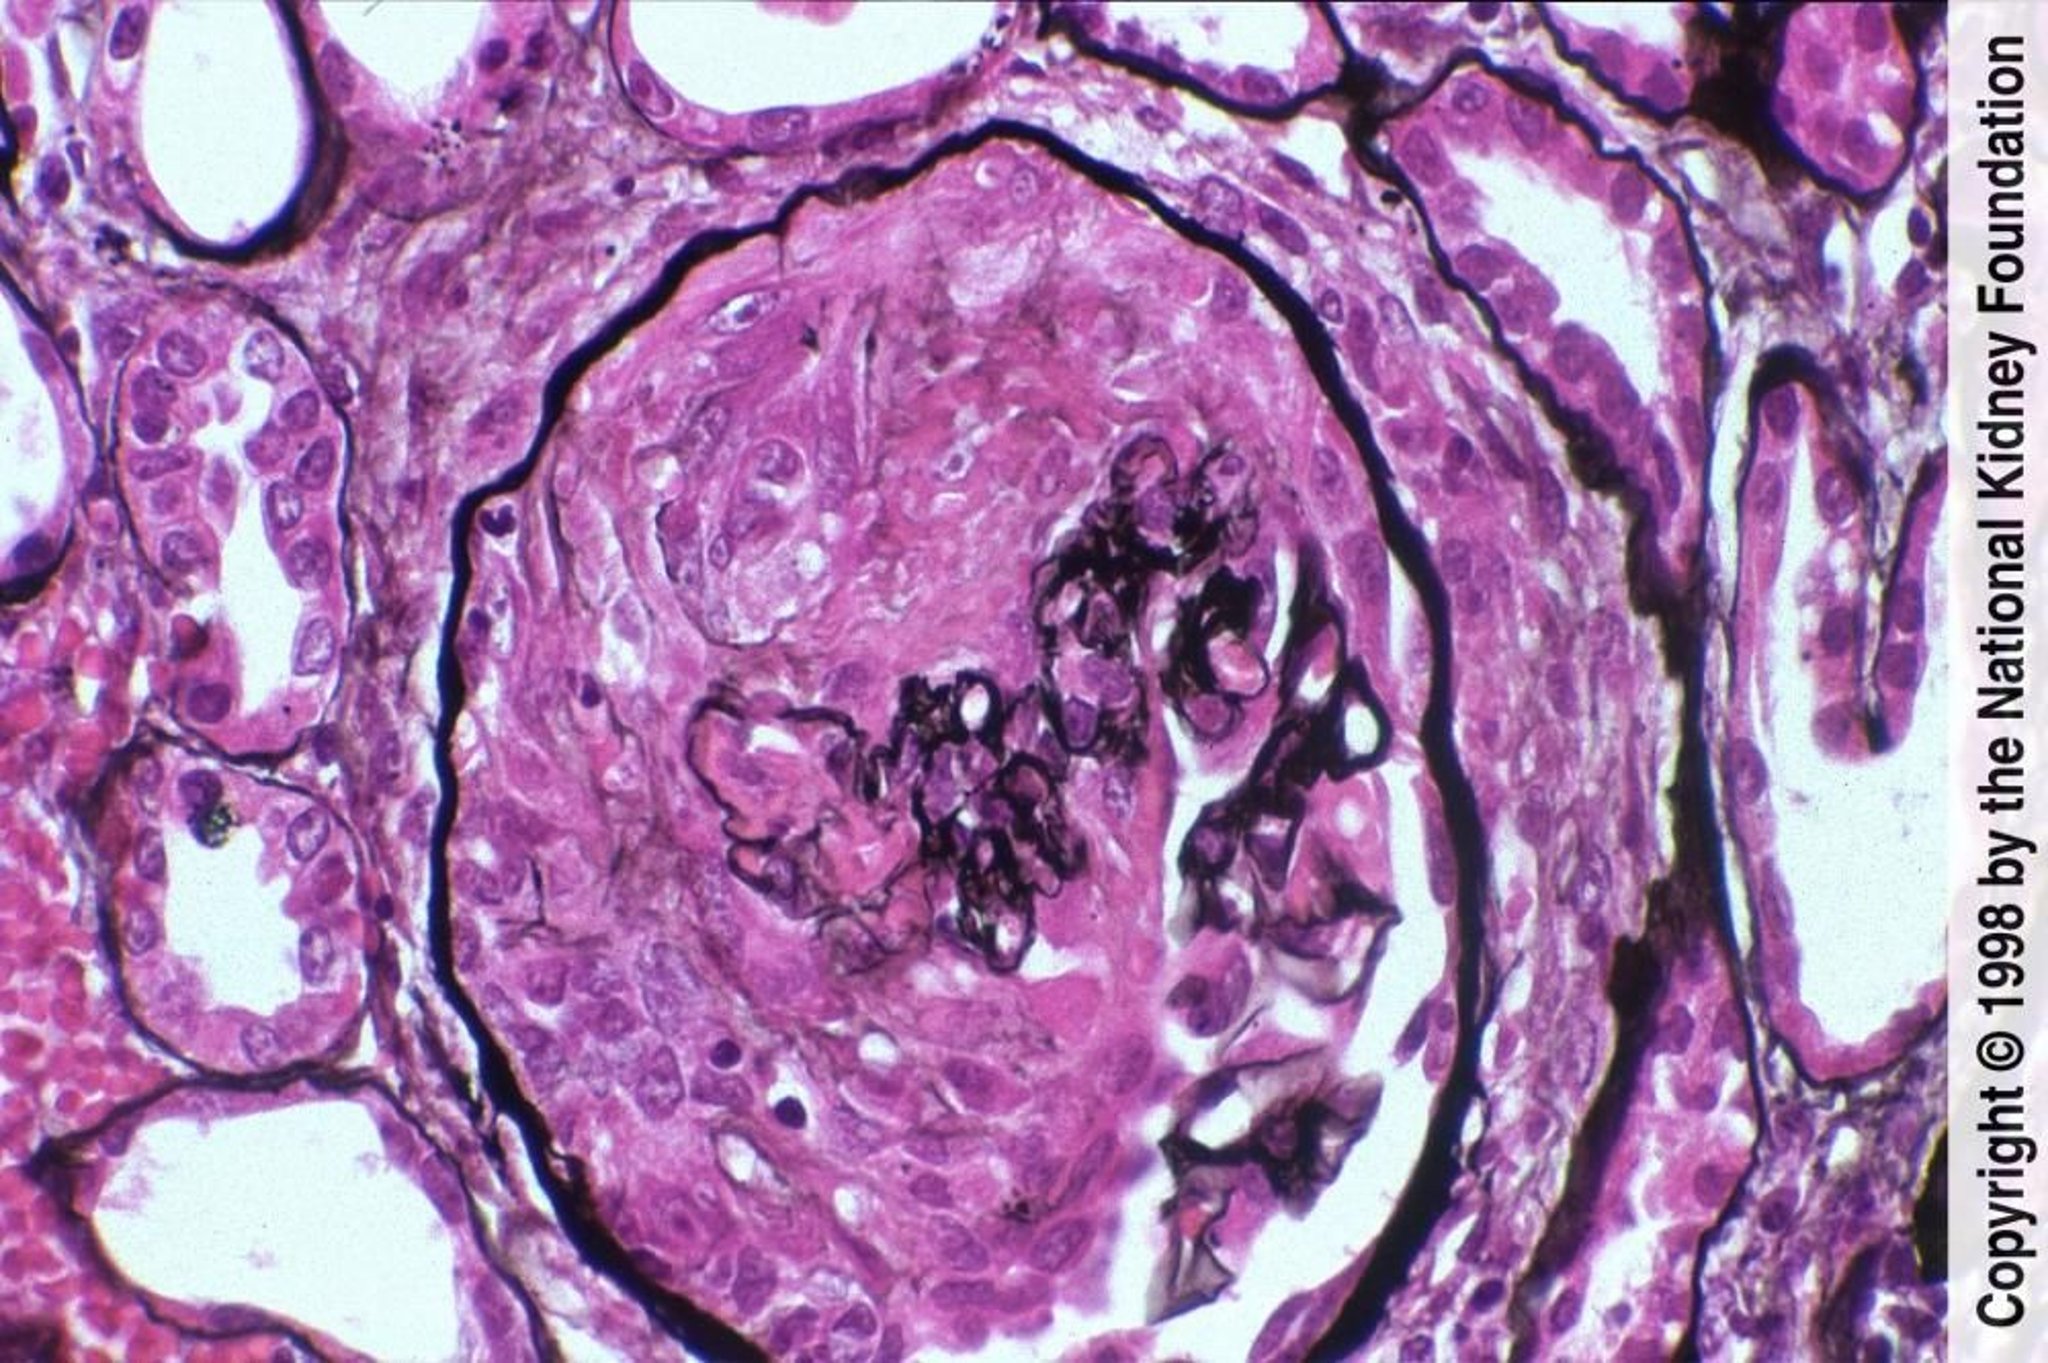

急速進行性糸球体腎炎(pauci-Immune型)

pauci-immune型の特徴は,フィブリノイド壊死を伴う半月体形成および蛍光抗体染色法で陰性となることである(PAM染色,400倍)。

Image provided by Agnes Fogo, MD, and the American Journal of Kidney Diseases' Atlas of Renal Pathology (see www.ajkd.org).